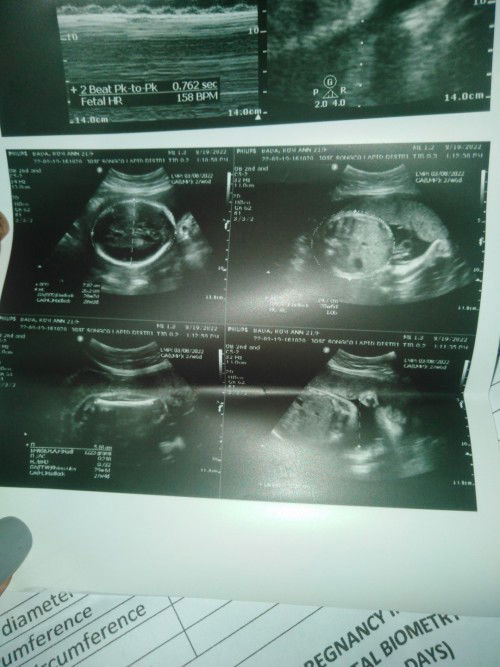

27weeks napo ako preggy mga momshi. Normal lang puba na sumasakit ang balakang at taas ng puwerta ko? Pag nakahiga ako hindi ako maka tagilid o maka tayo agad sa sobrang sakit ng balakang ko. At pag tatayo ako nag tutunugan yung mga buto ko sa taas ng pwerta. Normal lang poba ito mga momshi? #f1sTymMom